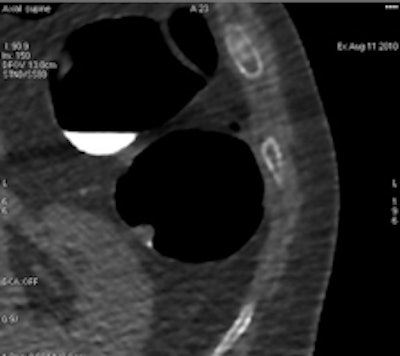

Acute ileal involvement by Crohn's disease, with wall thickening and mucosal enhancement.